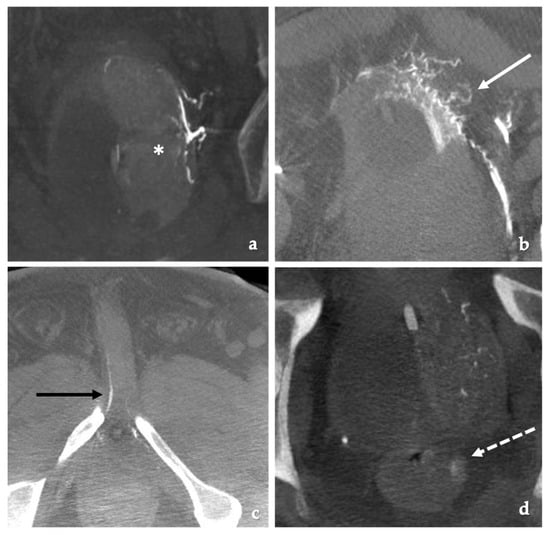

4.2. Procedure